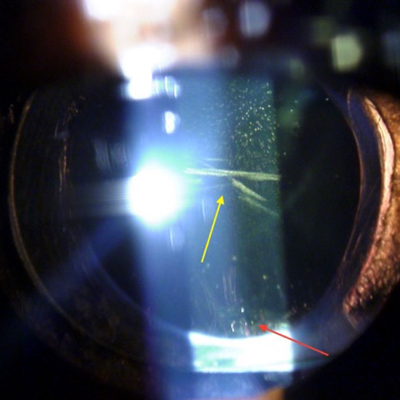

Eric Donnenfeld, MD, Rockville Centre, New York, said: This patient has three significant problems that are all likely contributing to his problem of glare and halo: IOL opacifications, hyperopic refractive error, and a fixed dilated pupil. The cataract surgery was otherwise done well and the 1-piece acrylic IOL is in the bag.